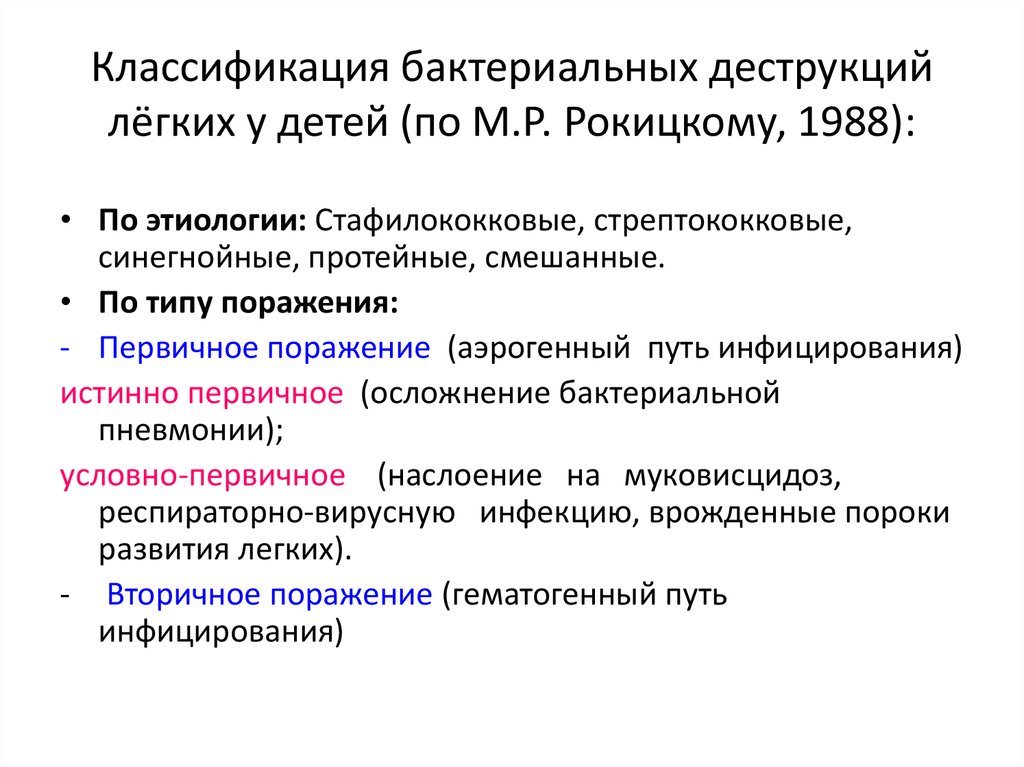

Бактериальная деструкция легких у детей презентация - 88 фото